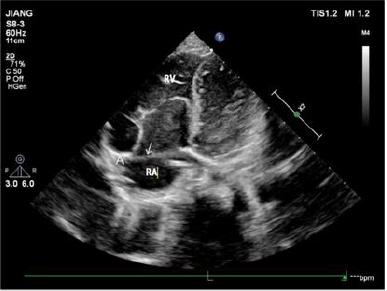

Note: RV right ventricle; RA right atrium

Figure 1: The apical four-chamber view showing that the arrow points to the front of the tricuspid valve annulus. A is the attachment point of the anterior tricuspid valve on the annulus. In the picture, the anterior tricuspid valve is attached to the anterior part of the tricuspid annulus, and the position is normal.